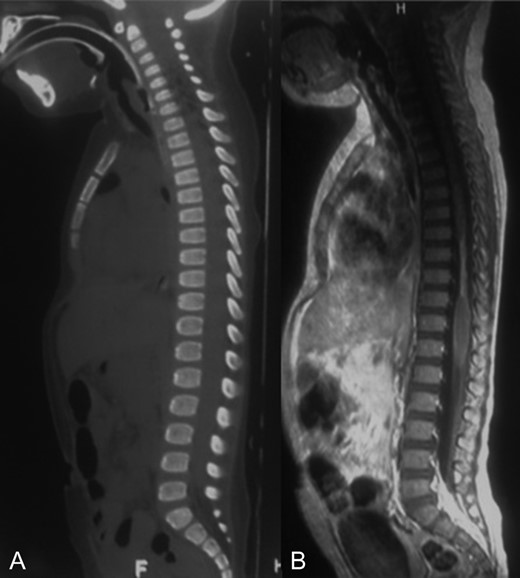

MRI showed a narrowing lesion of the spinal cord from T7 to T10 (Figs 1B, 2A and B).

A-B: A. Sagittal T1 sequence showing a narrowed spinal cord from T7 to T10. B. Sagittal STIR-weighted MRI of the thoracic spine showing chronic appearance of a string-like atrophic cord.